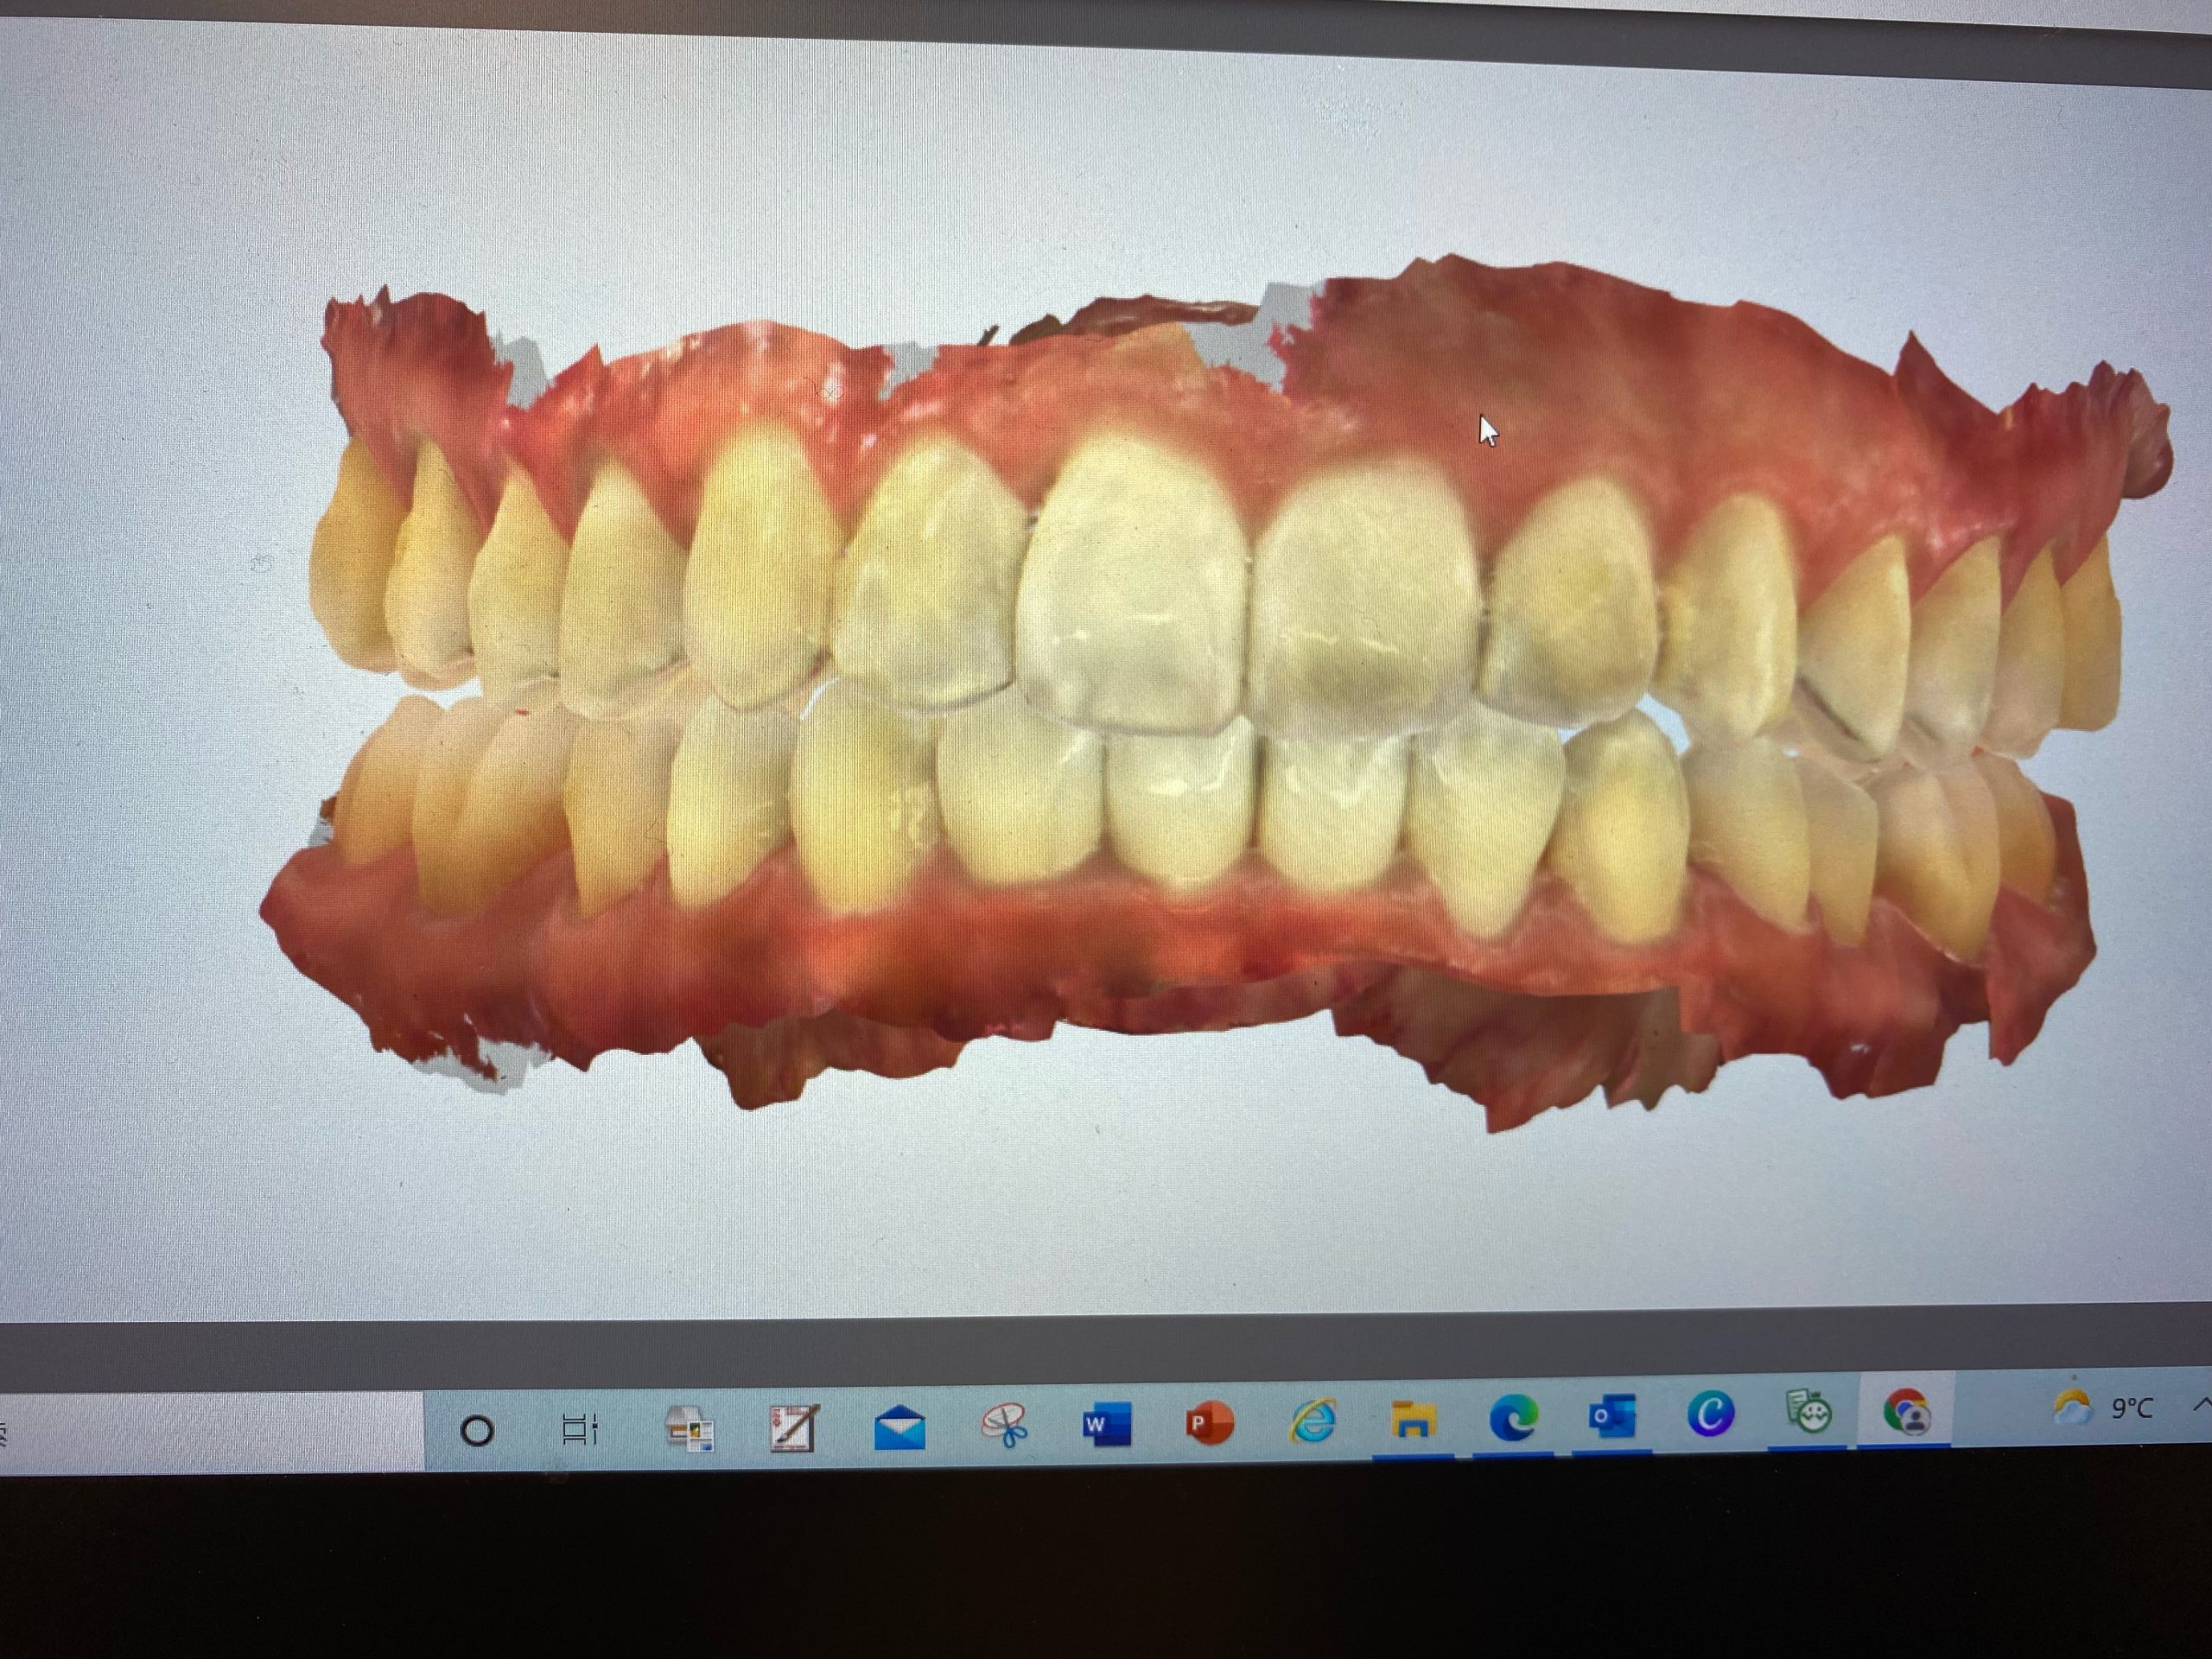

3Dスキャナーで一歩先を行く診療を実現 2022.1.1

マウスピース矯正、インビザラインの矯正装置を作製する時『iTero Element(アイテロ エレメント)』という3Dスキャナーで採取しています。

この『iTero』の導入で快適にしかも精密に歯型をとることができます。

単なる口腔内スキャナーではなく

・口腔内カラー写真

・経時的変化を記録することで患者様により理解して頂けます

・歯がどのように動いていくかのシュミレーションシステム

矯正だけでなく嚙み合わせが不調の方も先進的な視覚化ツールで患者様は御自身の口腔内状態についてリアルタイムで知ることができます。